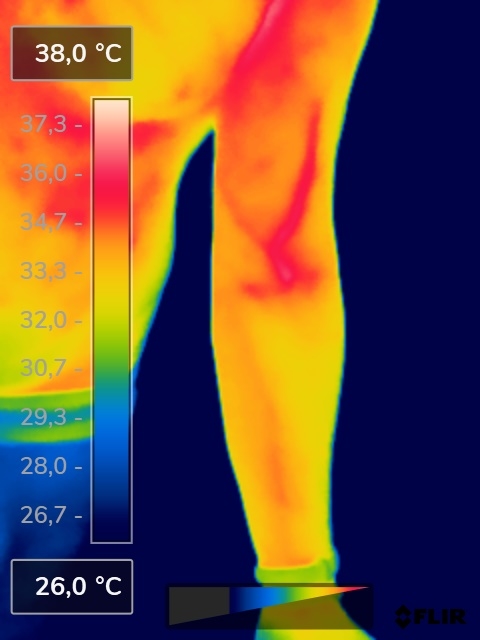

Como na sequência de termogramas abaixo de um paciente do sexo masculino, de 44 anos, sem comorbidades e praticante de atividade física que apresentou fortes dores em braço esquerdo (com irradiação para antebraço) após treino de musculação. Esta dor chegou a ser incapacitante, pois impossibilitava inclusive o paciente a realizar atividades de vida diárias como pegar um copo de água.

Após a realização de uma Análise Termofuncional©®, foi detectado alterações térmicas em “linha”, margeando as fibras musculares e tendíneas inferiores (insercionais) bicipitais. Estas alterações também aventaram a hipótese de dilatação venosa, por alguma reação inflamatória local. Foi realizado então aplicação de laserterapia através da Técnica Termoguiada, que acabou por promover a completa analgesia em 24 horas após aplicação.